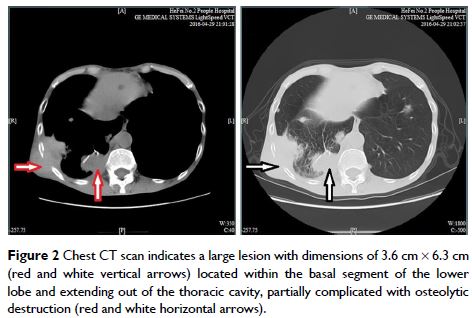

Case Report

- 作者:Jinling Bi, Haiyuan Liu, Yong Huang

- 期刊:International Medical Case Reports Journal